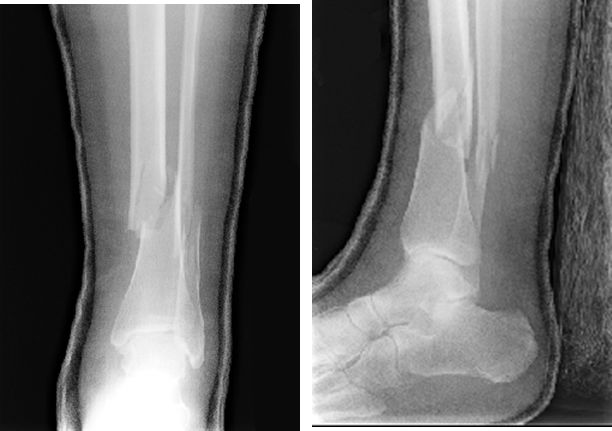

MaisonneuveFracture

• 腓骨中段骨折

• 下胫腓分离